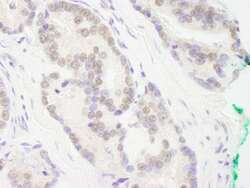

Supportive validation

- Submitted by

- LSBio (provider)

- Enhanced method

- Genetic validation

- Main image

- Experimental details

- Detection of Human RCOR3 by Immunohistochemistry. Sample: FFPE section of human breast carcinoma. Antibody: Affinity purified rabbit anti-RCOR3 used at a dilution of 1:250.

- Submitted by

- LSBio (provider)

- Enhanced method

- Genetic validation

- Main image

- Experimental details

- Detection of Human RCOR3 by Immunohistochemistry. Sample: FFPE section of human prostate carcinoma. Antibody: Affinity purified rabbit anti-RCOR3 used at a dilution of 1:250.